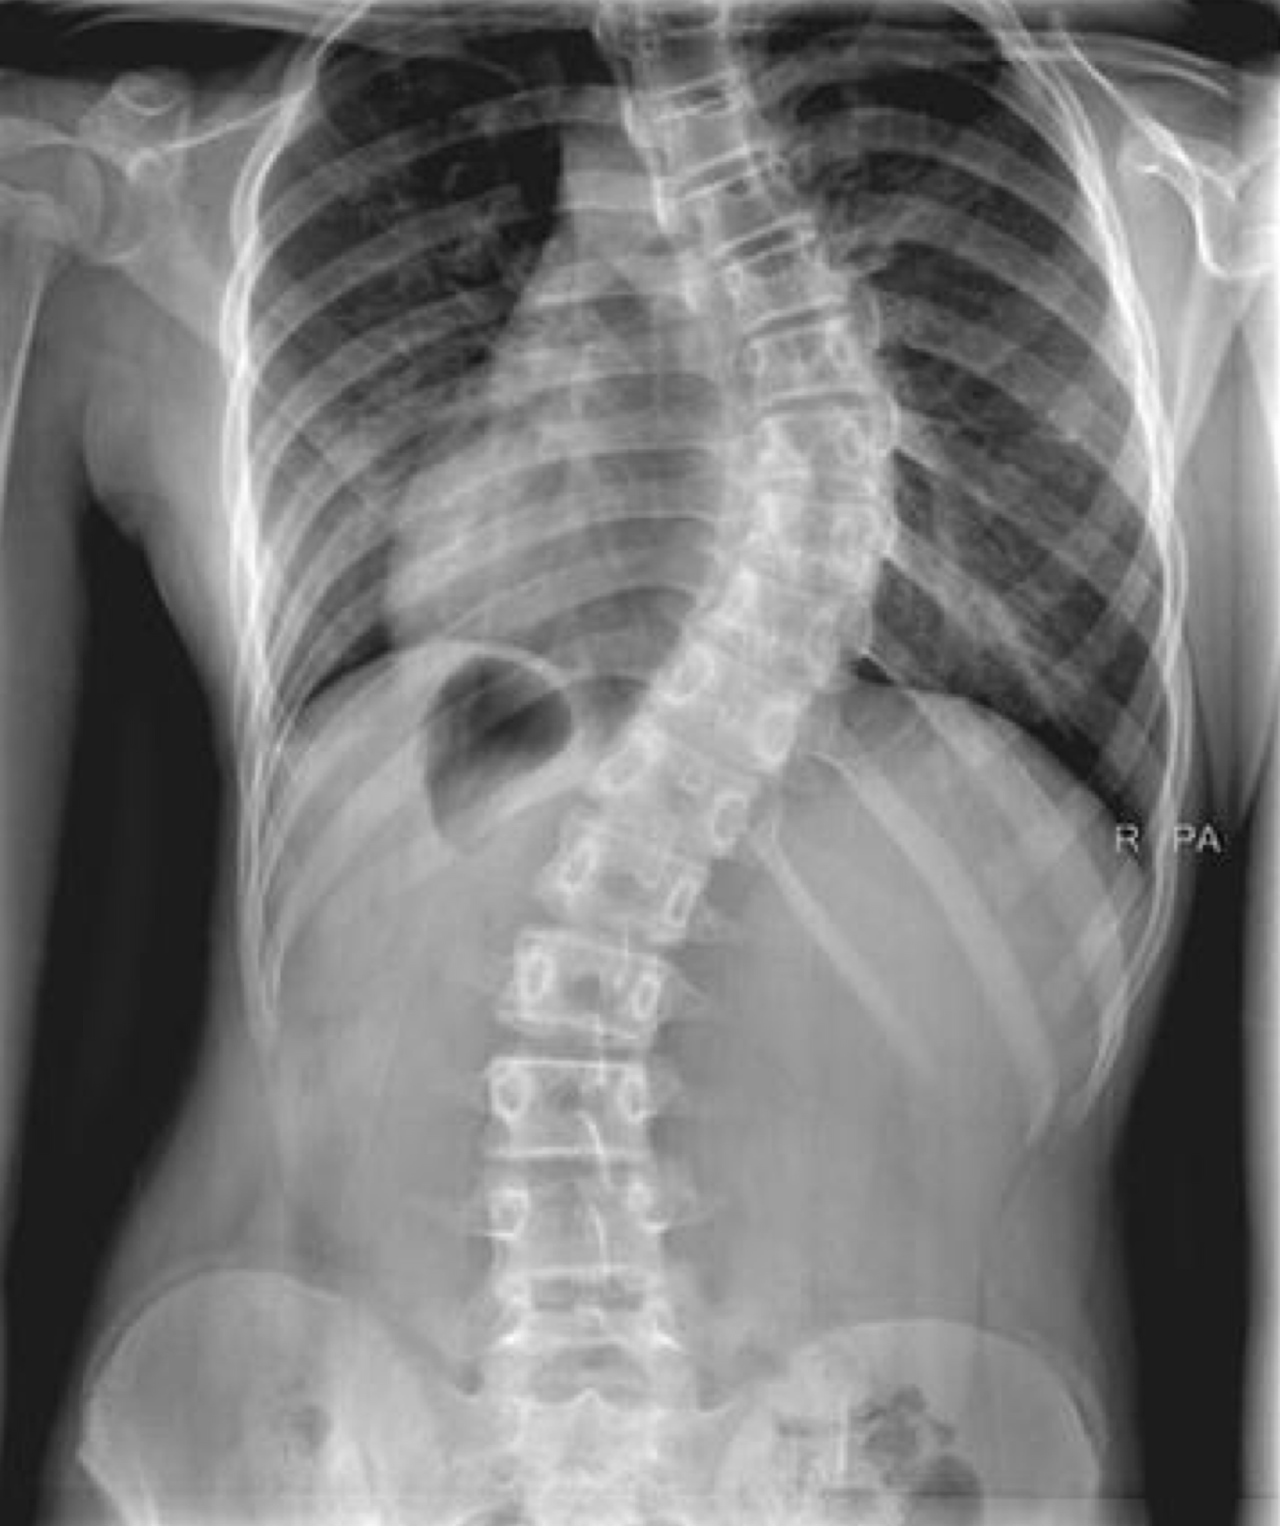

An X-ray of the spine can help doctors to confirm the diagnosis of scoliosis, measure the degree of the spinal curve and ascertain the maturity of the child's skeleton.

The degree of the spinal curve will determine the severity of scoliosis: mild, moderate or severe scoliosis. Mild curves less than 10 degrees are not considered as scoliosis and deemed to be insignificant.